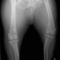

■ 症例22 ポメラニアン 1歳5か月 去勢雄

左後肢の挙上を主訴に来院した。整形学的検査、レントゲン検査より左右の膝蓋骨脱臼(左GradeⅡ〜Ⅲ、右Grade Ⅱ)を認めた。また、脛骨の前方引き出し試験の際に、引き出し兆候は認められないものの、疼痛が認められたため、前十字靭帯の損傷が疑われた。術中における、目視および関節内の操作によって、前十字靭帯の損傷や過伸展といった異常が認められなかったため、膝蓋骨脱臼の整復のみ実施した。手術手技は縫工筋及び内側広筋の解放、脛骨粗面の外側転位、滑車ブロック形造溝術、内外側関節包の縫縮を実施した。本症例は跛行もなく経過良好である。しかし、頸骨高平部の角度(TPA)が 右26.2°、左24.9°であり、解剖学的に前十字靭帯損傷のリスクが高いことから今後の経過に注意が必要である。